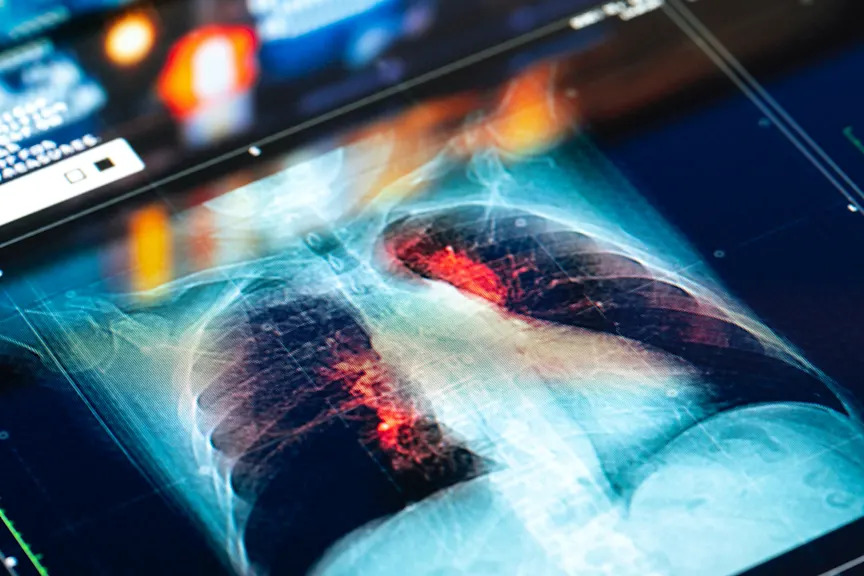

肺癌治疗的康复策略

它估计了据美国临床肿瘤学会(ASCO)称,235,760名美国成年人将于2021年诊断患有肺癌。肺癌治疗可以激烈,无论您的医生都建议哪种治疗方式,但它是恢复,可以抛出许多人的循环。Newsflash:恢复很努力!为了帮助您留下生存的道路,无论哪种可能对您看起来像是什么样的,我们要求专家为他们的最佳策略进行肺癌治疗尽可能简单地进行复苏。